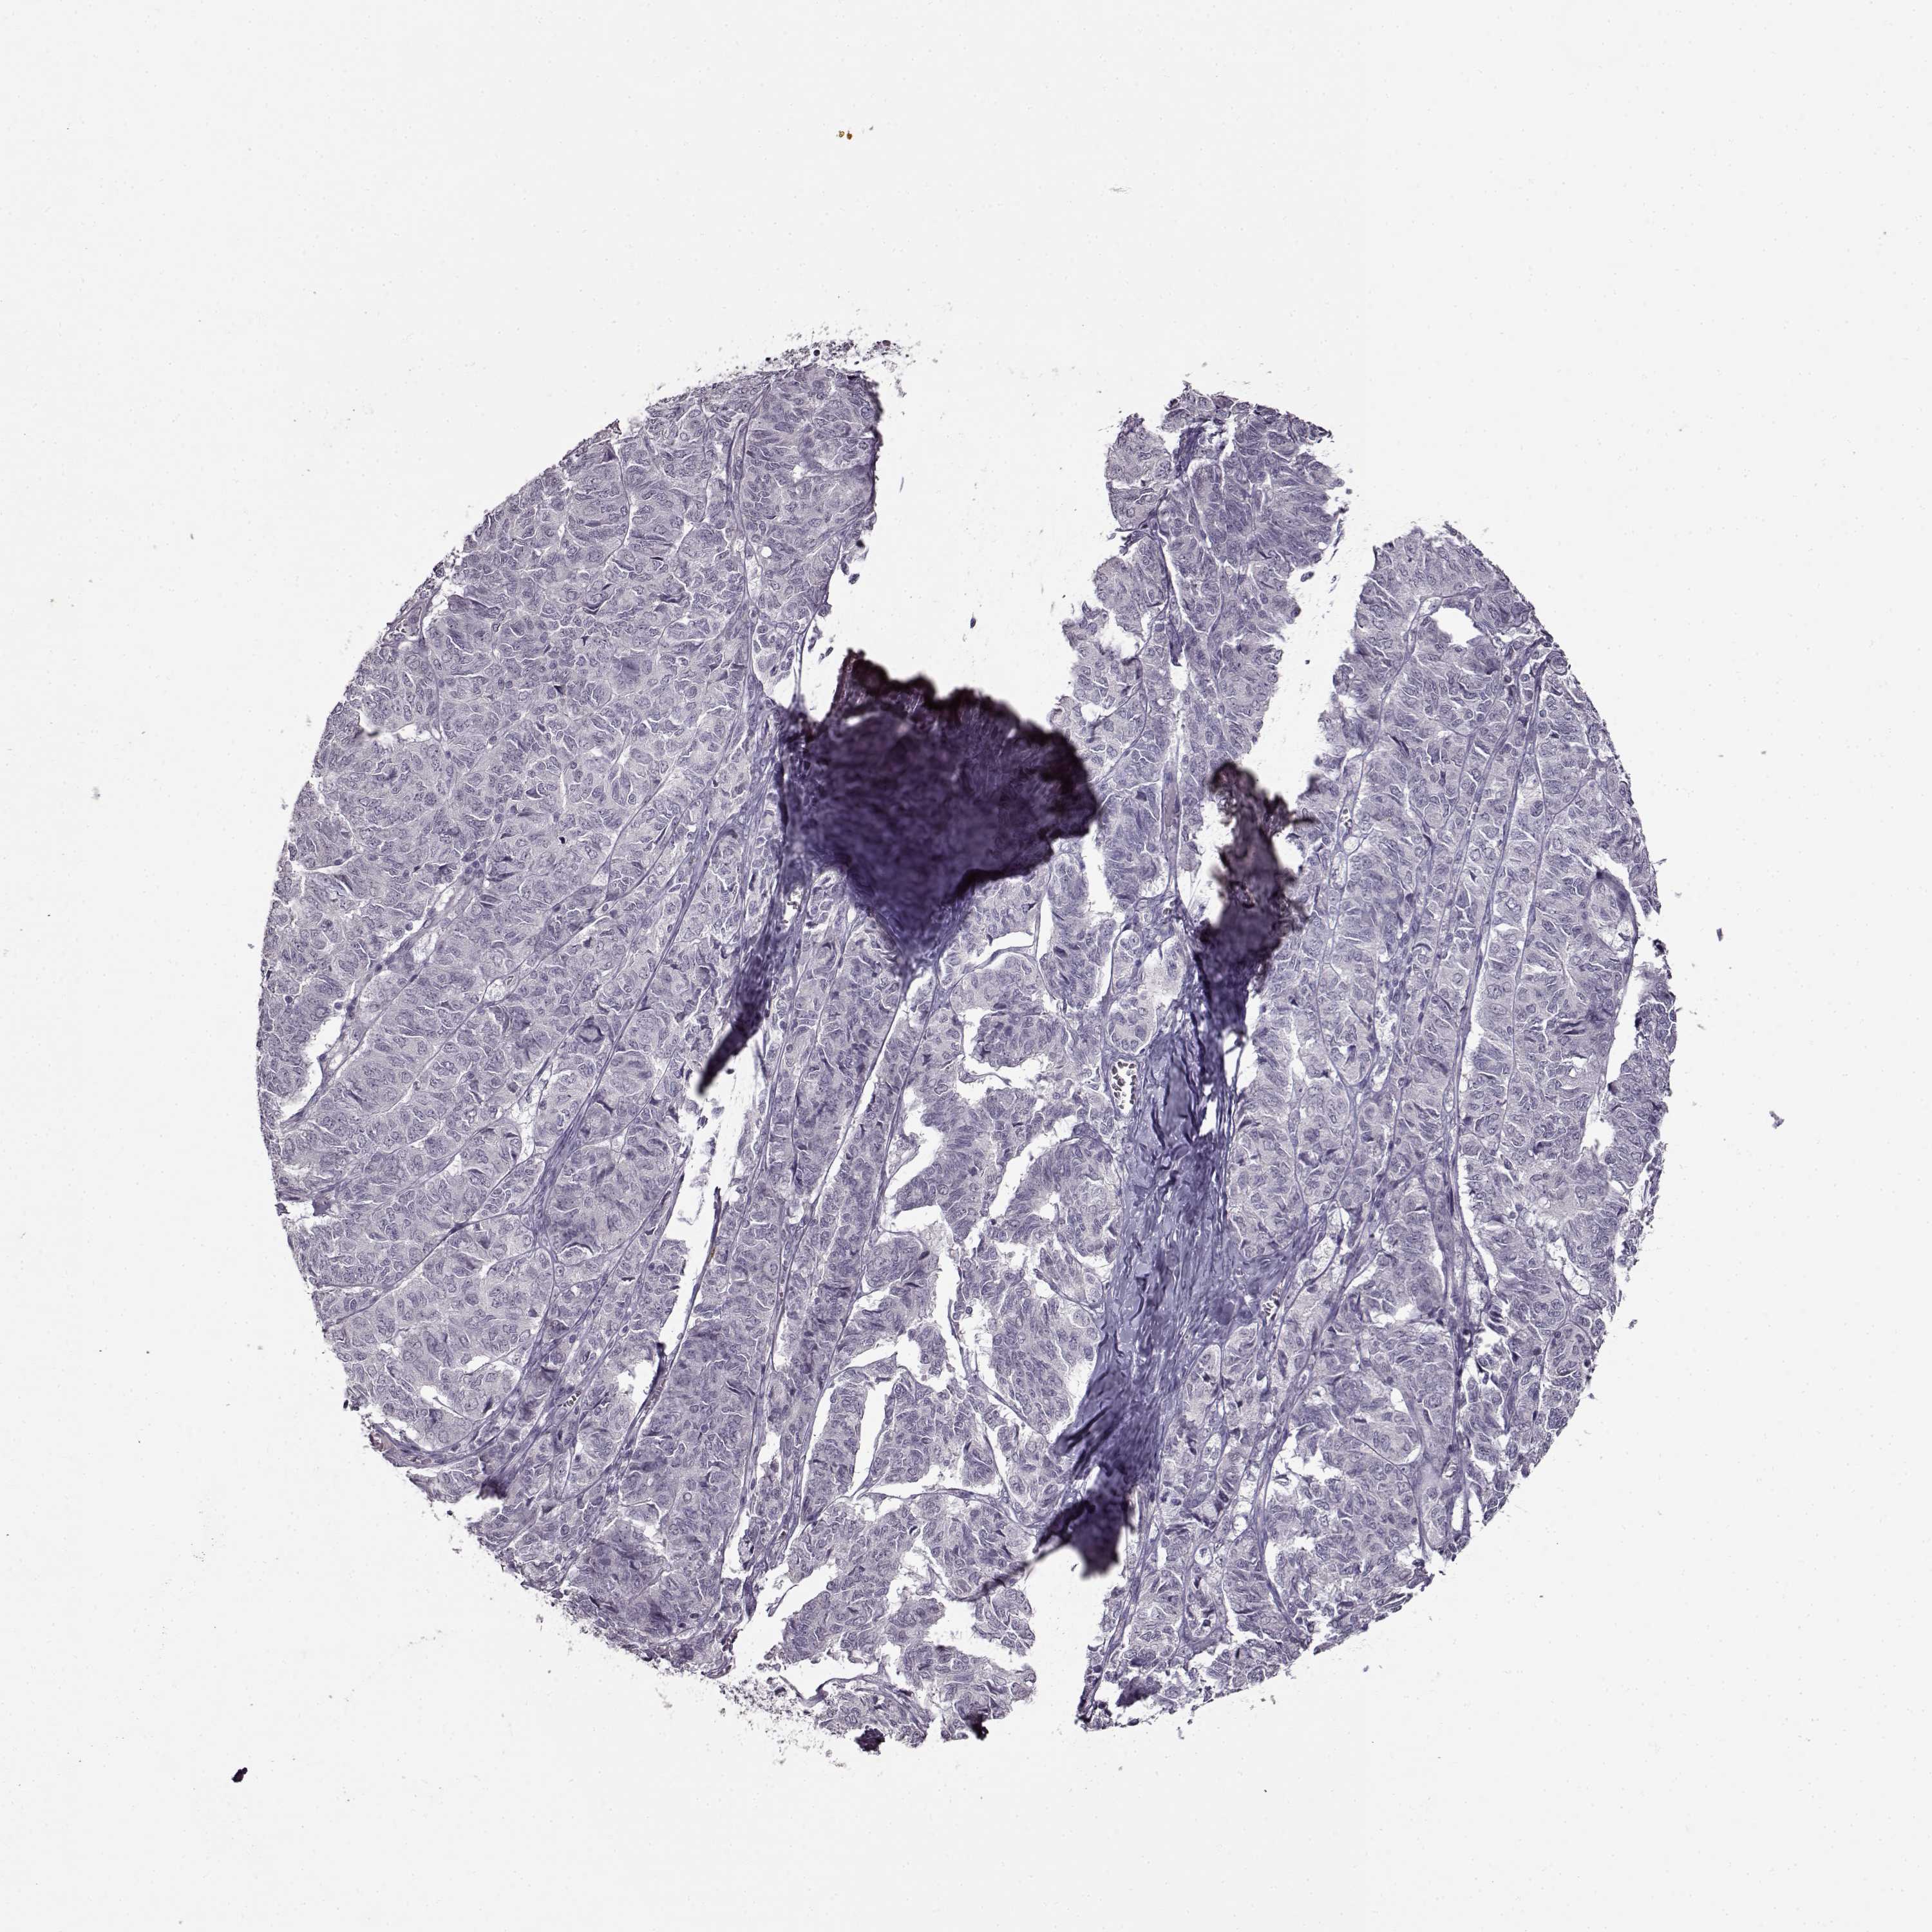

OVARIAN CANCER - Protein expressioni

A mouse-over function shows sample information and annotation data. Click on an image to view it in a full screen mode. Samples can be filtered based on level of antibody staining by selecting one or several of the following categories: high, medium, low and not detected. The assay and annotation is described here.

Note that samples used for immunohistochemistry by the Human Protein Atlas do not correspond to samples in the TCGA dataset.

Antibody stainingi

Antibody staining in the annotated cell types in the current human tissue is reported as not detected, low, medium, or high, based on conventional immunohistochemistry profiling in selected tissues. This score is based on the combination of the staining intensity and fraction of stained cells.

Each image is clickable and will lead to virtual microscopy that enables deeper exploration of all samples and also displays staining intensity scores, fraction scores and subcellular localization as well as patient and tissue information for each sample.

Antibody HPA069703

Antibody CAB023410

Staining

High

Medium

Low

Not detected

Intensity

Strong

Moderate

Weak

Negative

Quantity

>75%

75%-25%

<25%

None

Location

Nuclear

Cytoplasmic/membranous

Cytoplasmic/membranous,nuclear

Cystadenocarcinoma, serous, NOS

Cystadenocarcinoma, mucinous, NOS

Carcinoma, endometroid